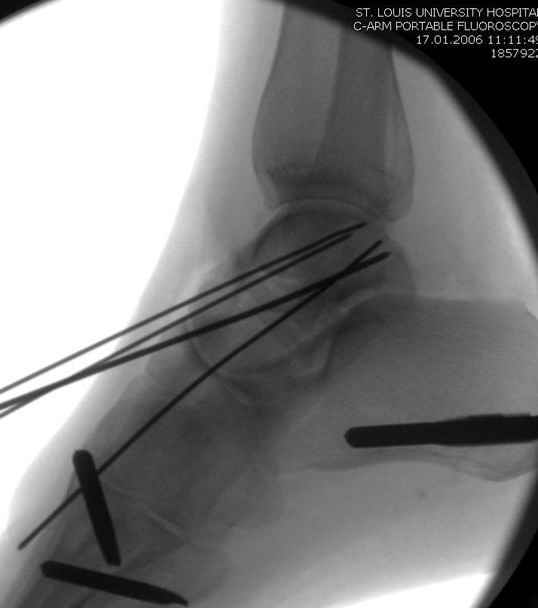

Вдогонку по поводу перелома таранной кости, больная 81, не страдает диабетом, перелом закрытый, в первый же день поступления ограничились временным наружным фиксатором (как на снимке).

Планировалась открытая фиксация после спадения отека, но больная пожелала лечиться по месту жительству в другом штате..

За пару недель насчитал 5 больных с переломом таранной кости, из них двое с двусторонним повреждением.

Из-за отека на стопе тактика лечения у всех была

одинаковая: временная наружная фиксация до спадения отека, при изолированных переломах они выписывались домой и через дней 7 госпитализировались на оперативное лечение.

Примеры на снимке...